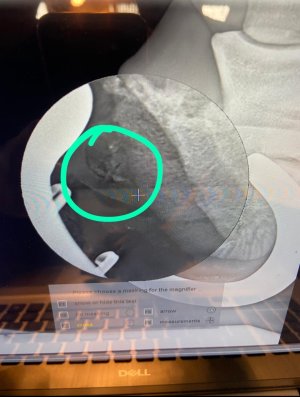

I see a face!An ultrasound this time.

Wow that's really interestingBlack holes on a scan have IME meant damaged suspensories, but I might be well off track on that.

Fractured jaw? Wired??

Is the first image showing a broken bone on the leg the left side?I’m liking this game… will try to dig out some horse ones (they aren’t as good as yours) but in the meantime please enjoy these bird ones (why did we have to PTS?)

Yep correct. If you compare them both you might be able to see the difference with no 2 (look for symmetry)Is the first image showing a broken bone on the leg the left side?